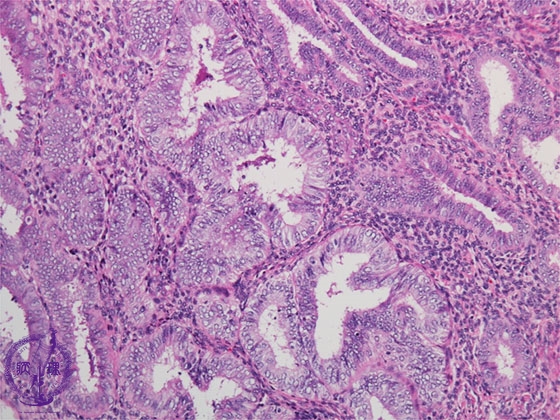

- ★(5)Complex endometrial hyperplasia

Histology (HE stain, intermediate power): Atypical endometrial hyperplasia, complex. Under the red dotted line, proliferation of endometrial glands with cytologic atypia (nuclear enlargement, rounded nuclei, enlarged nucleoli, disturbed nuclear arrangement), dense glandular arrangement and structural atypia (papillary structure, yellow arrow) is identifiable.